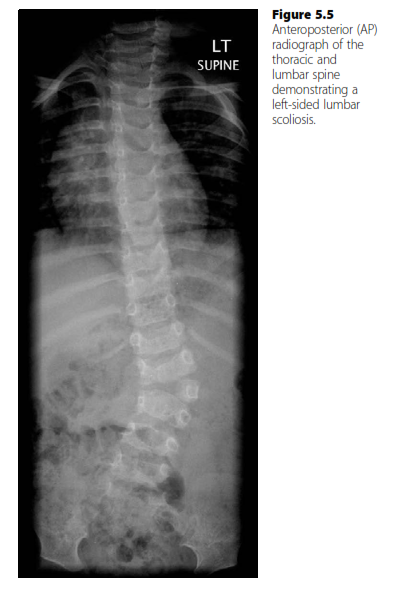

Structured oral examination question 4: Scoliosis EXAMINER : What can you see? ( Figure 5.5 .) CANDIDATE : Th…